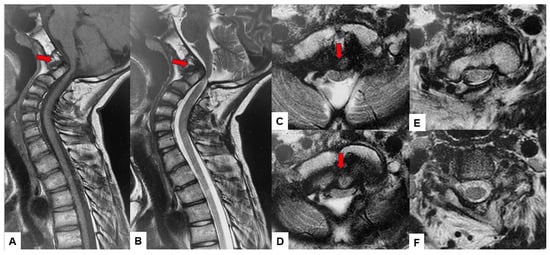

2.3. Preoperative Imaging

2.5. Postoperative Imaging